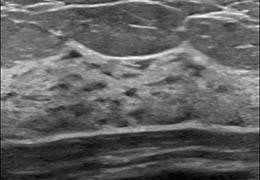

View X-Ray CT & MRI Scans Fast and Easily

FREE and easy to use 3D DICOM Viewer – for surgeons and patient education

Designed for surgeons, Pro Surgical 3D makes it easy to view patient scans quickly. Pro Surgical 3D facilitates the optimal 3D treatment and assessment workflows based on X-ray CT and MRI scans – and best of all, it’s FREE!

Designed mainly for CT and MR DICOM modalities.

Multi-planar slicing.

Oblique slicing.